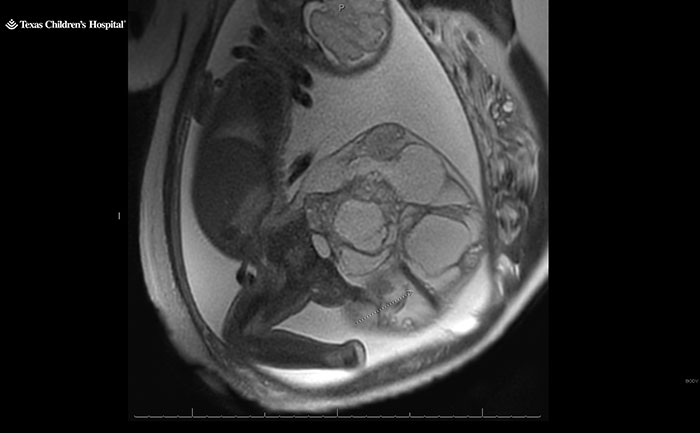

A 16-centimeter, four-pound (approximately 1.8-kilogram) fetal tumor was successfully removed from a baby’s tailbone. Born at 34 weeks, Adalida Tyler survived a sacrococcygeal teratoma tumor, a “very rare” condition that occurs in one in every 20,000 births.

A specialist subsequently diagnosed their unborn daughter with a sacrococcygeal teratoma instead, a rare fetal tumor that forms from the baby’s tailbone.

As they grow, the tumors can develop large blood vessels. “They basically steal the blood supply from the baby,” Dr. Nassr explained. “The heart of the baby needs to work very hard,” which, he said, can lead to heart failure.

On May 21, at 34 weeks, Kristin delivered Adalida via C-section. The little baby girl was born with the dreaded four-pound tumor, nearly two-thirds of her body weight.

Combined, the baby and tumor weighed more than 10 pounds (approximately 4.5 kilograms). Dr. Nassr recalled the tumor size being “a little bit smaller than a watermelon,” but larger than a cantaloupe.

He told People: “It was a big tumor, that’s why we were so worried. “We needed to be very careful during delivery.

“We had to avoid any trauma or rupture of the tumor. Because sometimes with that large of a tumor, it can rupture and can start bleeding, and baby can become very sick after delivery.”